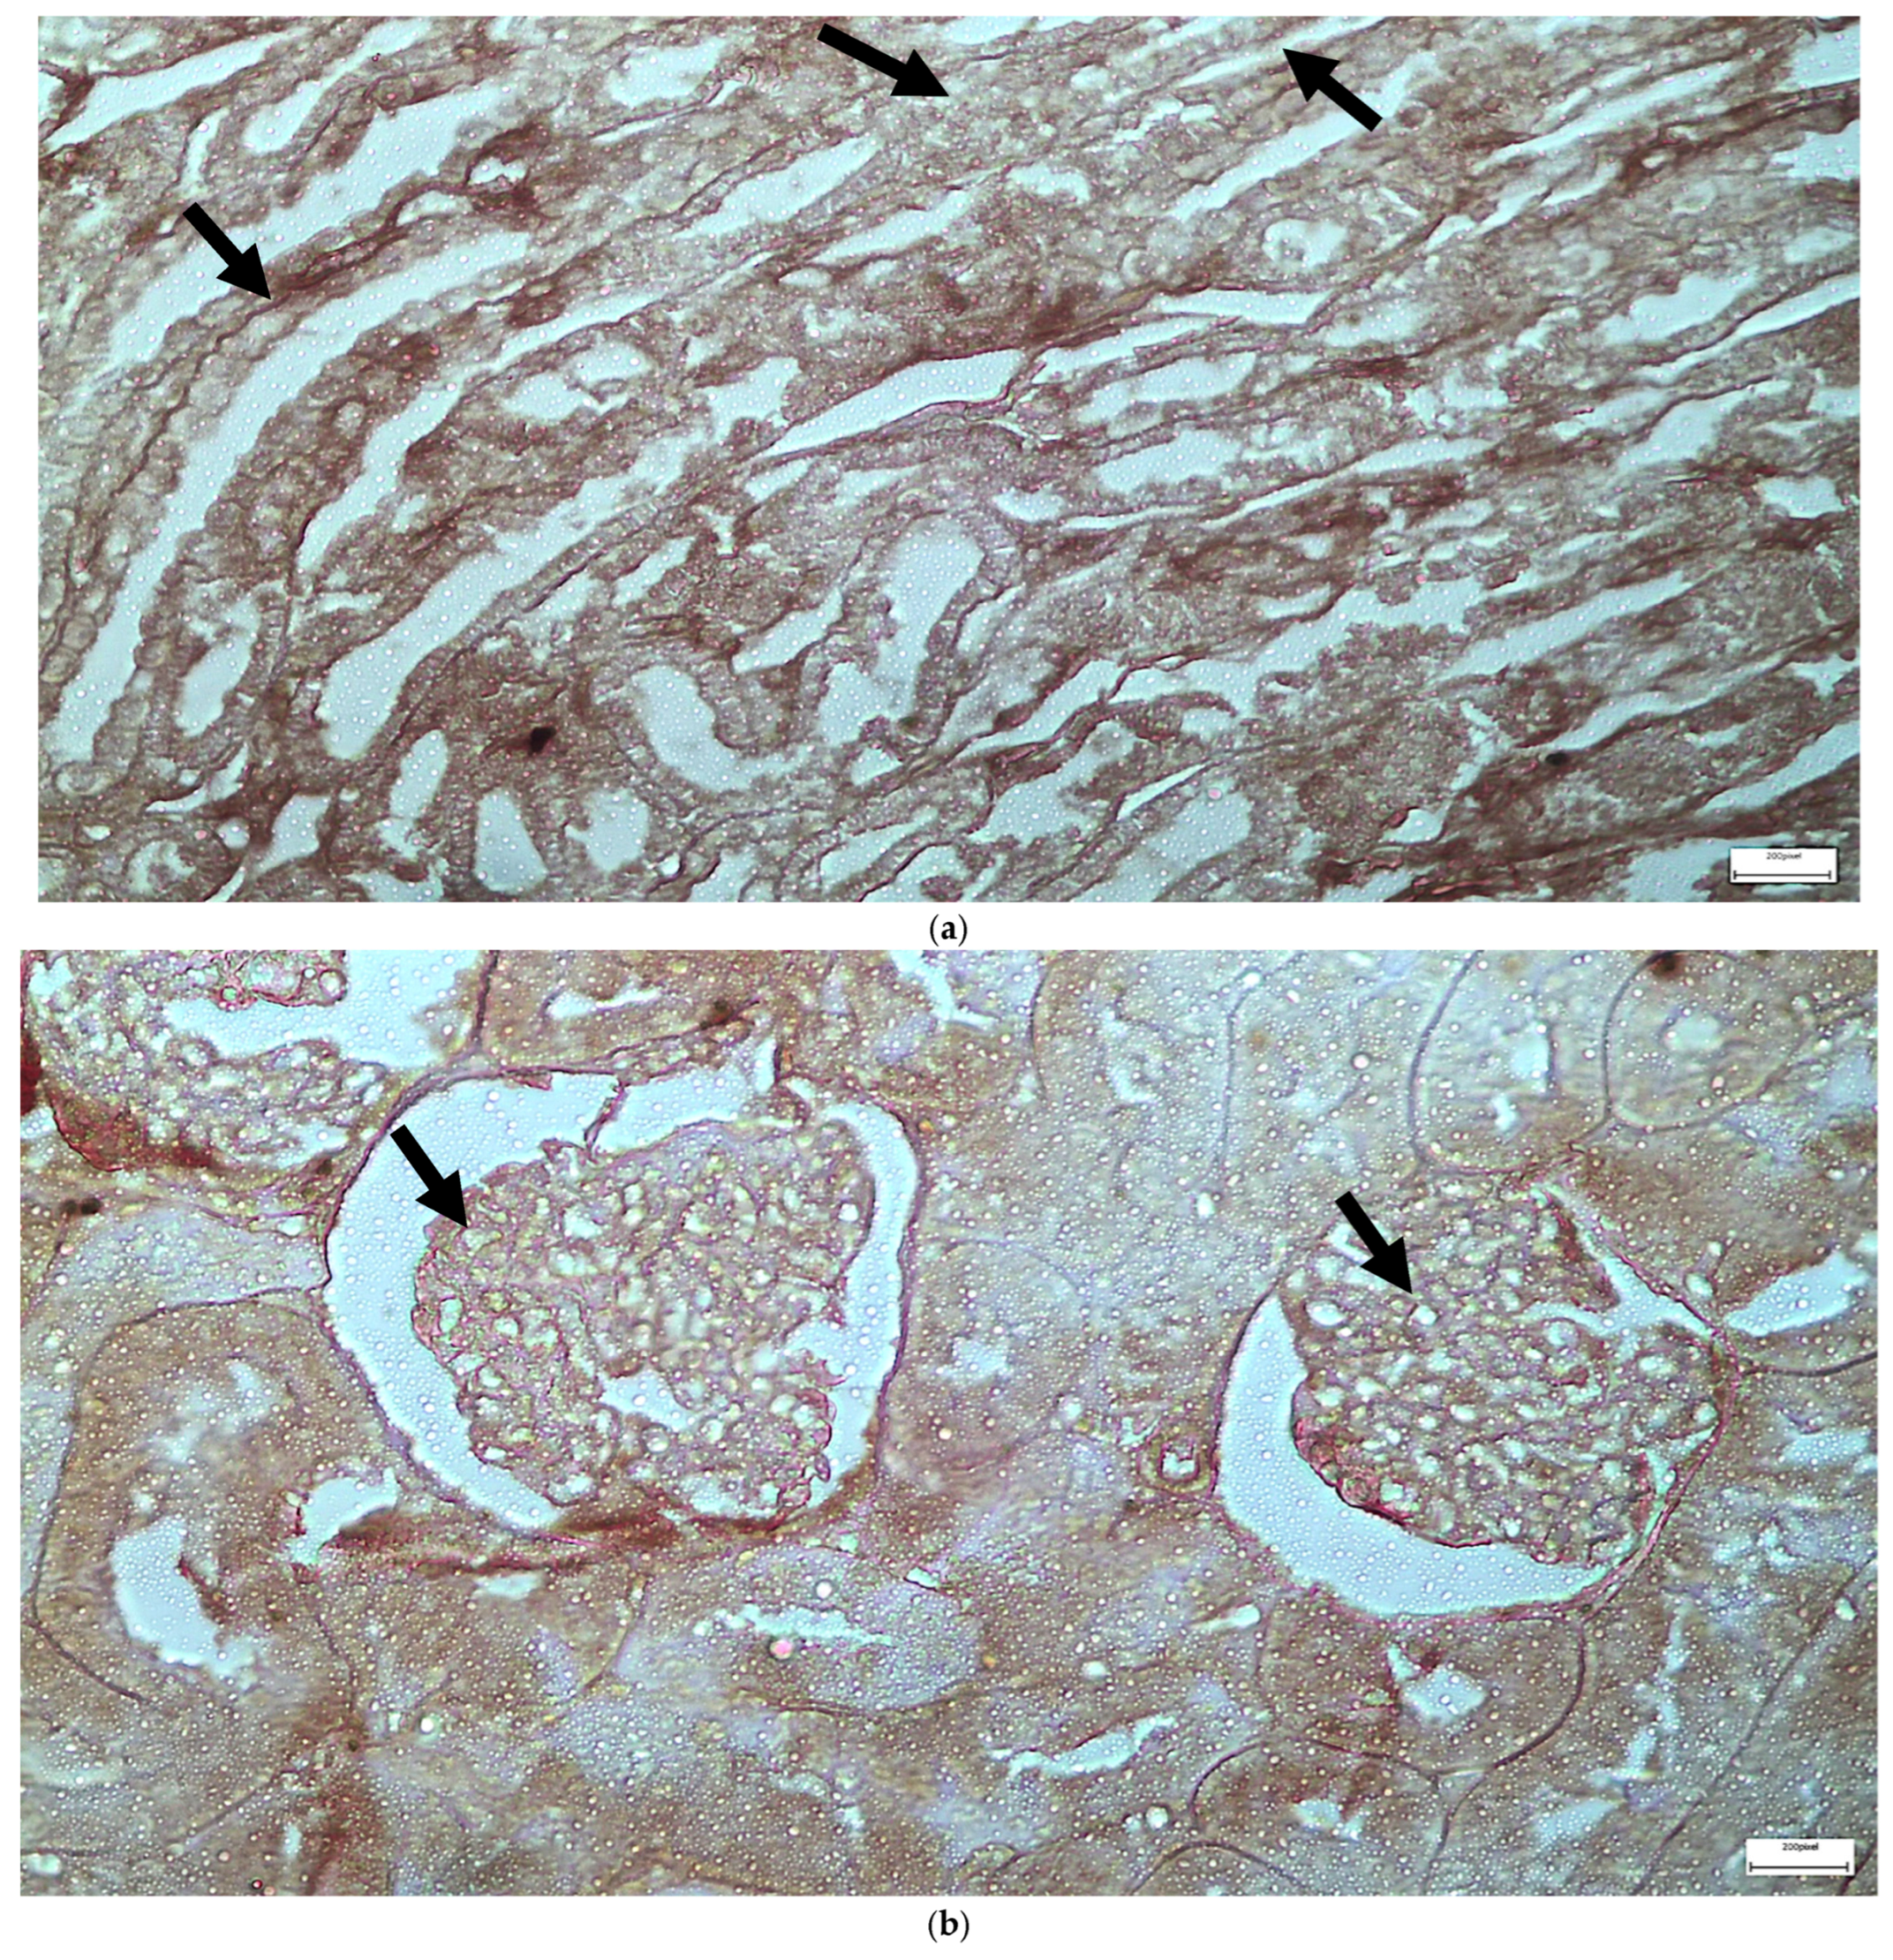

| C | Renal tubules and corpuscles | IL-6 | 1 | 2 | 2 |

| C | Renal tubules and corpuscles | EGFR | 1 | 1 | 1 |

| V1 | Renal tubules | IL-6 | 2 | 4 | 8 |

| V1 | Renal corpuscles | IL-6 | 2 | 2 | 4 |

| V1 | Renal tubules | EGFR | 3 | 4 | 12 |

| V1 | Renal corpuscles | EGFR | 2 | 2 | 4 |

| V2 | Renal corpuscles | IL-6 | 2 | 1 | 2 |

| V2 | Renal tubules | IL-6 | 2 | 3 | 6 |

| V2 | Renal corpuscles | EGFR | 3 | 4 | 12 |

| V2 | Renal tubules | EGFR | 2 | 4 | 8 |

| M1 | Renal corpuscles | IL-6 | 2 | 3 | 6 |

| M1 | Renal tubules | IL-6 | 2 | 1 | 2 |

| M1 | Renal corpuscles | EGFR | 3 | 4 | 12 |

| M1 | Renal tubules | EGFR | 1 | 2 | 2 |

| M2 | Renal corpuscles | IL-6 | 3 | 3 | 9 |

| M2 | Renal tubules | IL-6 | 2 | 3 | 6 |

| M2 | Renal corpuscles | EGFR | 1 | 2 | 2 |

| M2 | Renal tubules | EGFR | 1 | 3 | 3 |

| VM | Renal corpuscles | IL-6 | 3 | 4 | 12 |

| VM | Renal tubules | IL-6 | 1 | 2 | 2 |

| VM | Renal corpuscles | EGFR | 3 | 3 | 9 |

| VM | Renal tubules | EGFR | 2 | 3 | 6 |